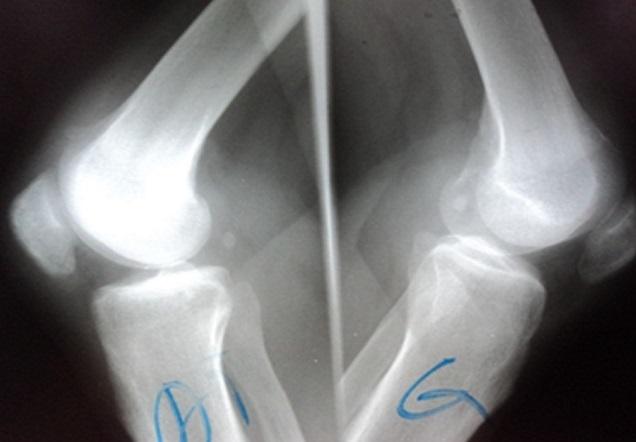

Spontaneous ruptures of the quadriceps tendon are infrequent injuries, it is seen primarily in patients with predisposing diseases such as gout, rheumatoid arthritis and chronic renal failure. A 32-year-old man had a history of end stage renal disease and received regular hemodialysis treatment for more than 5 years. He was admitted in our service for total functional impotence of the right lower limb with knee pain after a common fall two months ago. The radiogram showed a ''patella baja" with suprapatellar calcifications. The ultrasound and MRI showed an aspect of rupture of the quadriceps tendon in its proximal end with retraction of 3 cm. Quadriceps tendon repair was performed with a lengthening plasty, and the result was satisfactory after a serial rehabilitation program. The diagnosis of quadriceps tendon ruptures needs more attention in patients with predisposing diseases. They should not be unknown because the treatment of neglected lesions is more difficult. We insist on the early surgical repair associated with early rehabilitation that can guarantee recovery of good active extension.

股四头肌肌腱自发性断裂是一种罕见的损伤,主要见于患有痛风、类风湿性关节炎和慢性肾衰竭等易感疾病的患者。一名32岁男性有终末期肾病病史,接受规律血液透析治疗超过5年。两个月前他因一次普通跌倒后出现右下肢完全功能性阳痿伴膝关节疼痛而入住我院。X线片显示“低位髌骨”伴髌上钙化。超声和磁共振成像显示股四头肌肌腱近端有断裂迹象,回缩3厘米。采用延长成形术进行股四头肌肌腱修复,经过一系列康复计划后效果满意。对于患有易感疾病的患者,股四头肌肌腱断裂的诊断需要更多关注。不应忽视此类情况,因为治疗被忽视的损伤更加困难。我们坚持早期手术修复并结合早期康复,这可以保证良好的主动伸展恢复。